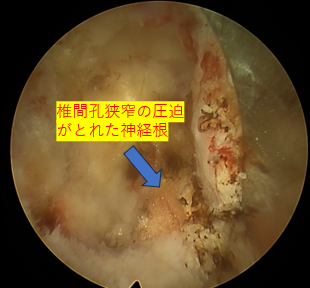

| 治療内容と方針 | 右下肢内側の痛み、しびれは後方固定除圧後の合併症である隣接椎間障害によるもので、右L4/5椎間孔の狭窄症が原因だったので「PEL(脊柱管狭窄症内視鏡下術)」を実施。神経を圧迫している骨をドリルで削開しました。削開後は、椎間孔狭窄の圧迫が取れて右L4神経根が確認できました。 それと同時に、神経修復作用の効果を期待できる血小板由来の成長因子を注入する「PRP療法」を行いました。 なお、他院で手術したL5/Sの部位は再発がないので、そこの部位の治療は行っていません。 |